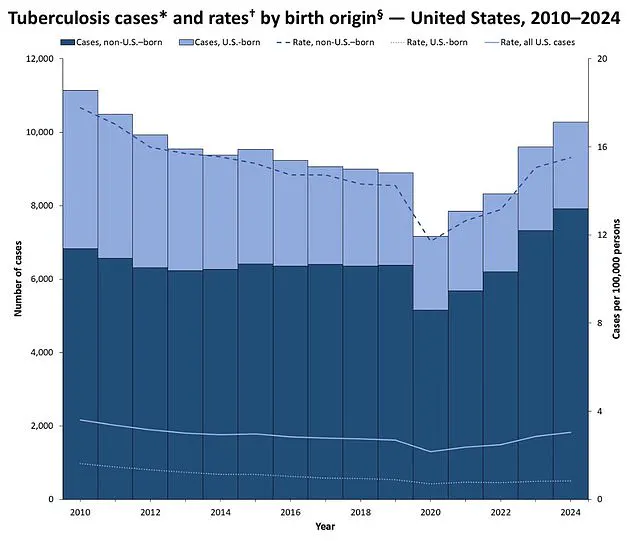

However, the recent spike in U.S. cases, with 10,347 infections reported in 2024—up 8% from the previous year and the highest since 2011—reveals a troubling trend in the developed world.

Yet, recent data from the CDC indicates that TB infections in the U.S. have reached their highest levels since 2011, signaling a reversal of this long-term decline.

According to the CDC, the majority of TB cases in the U.S. are linked to migration or imported infections, with most patients hailing from countries where TB is more prevalent.